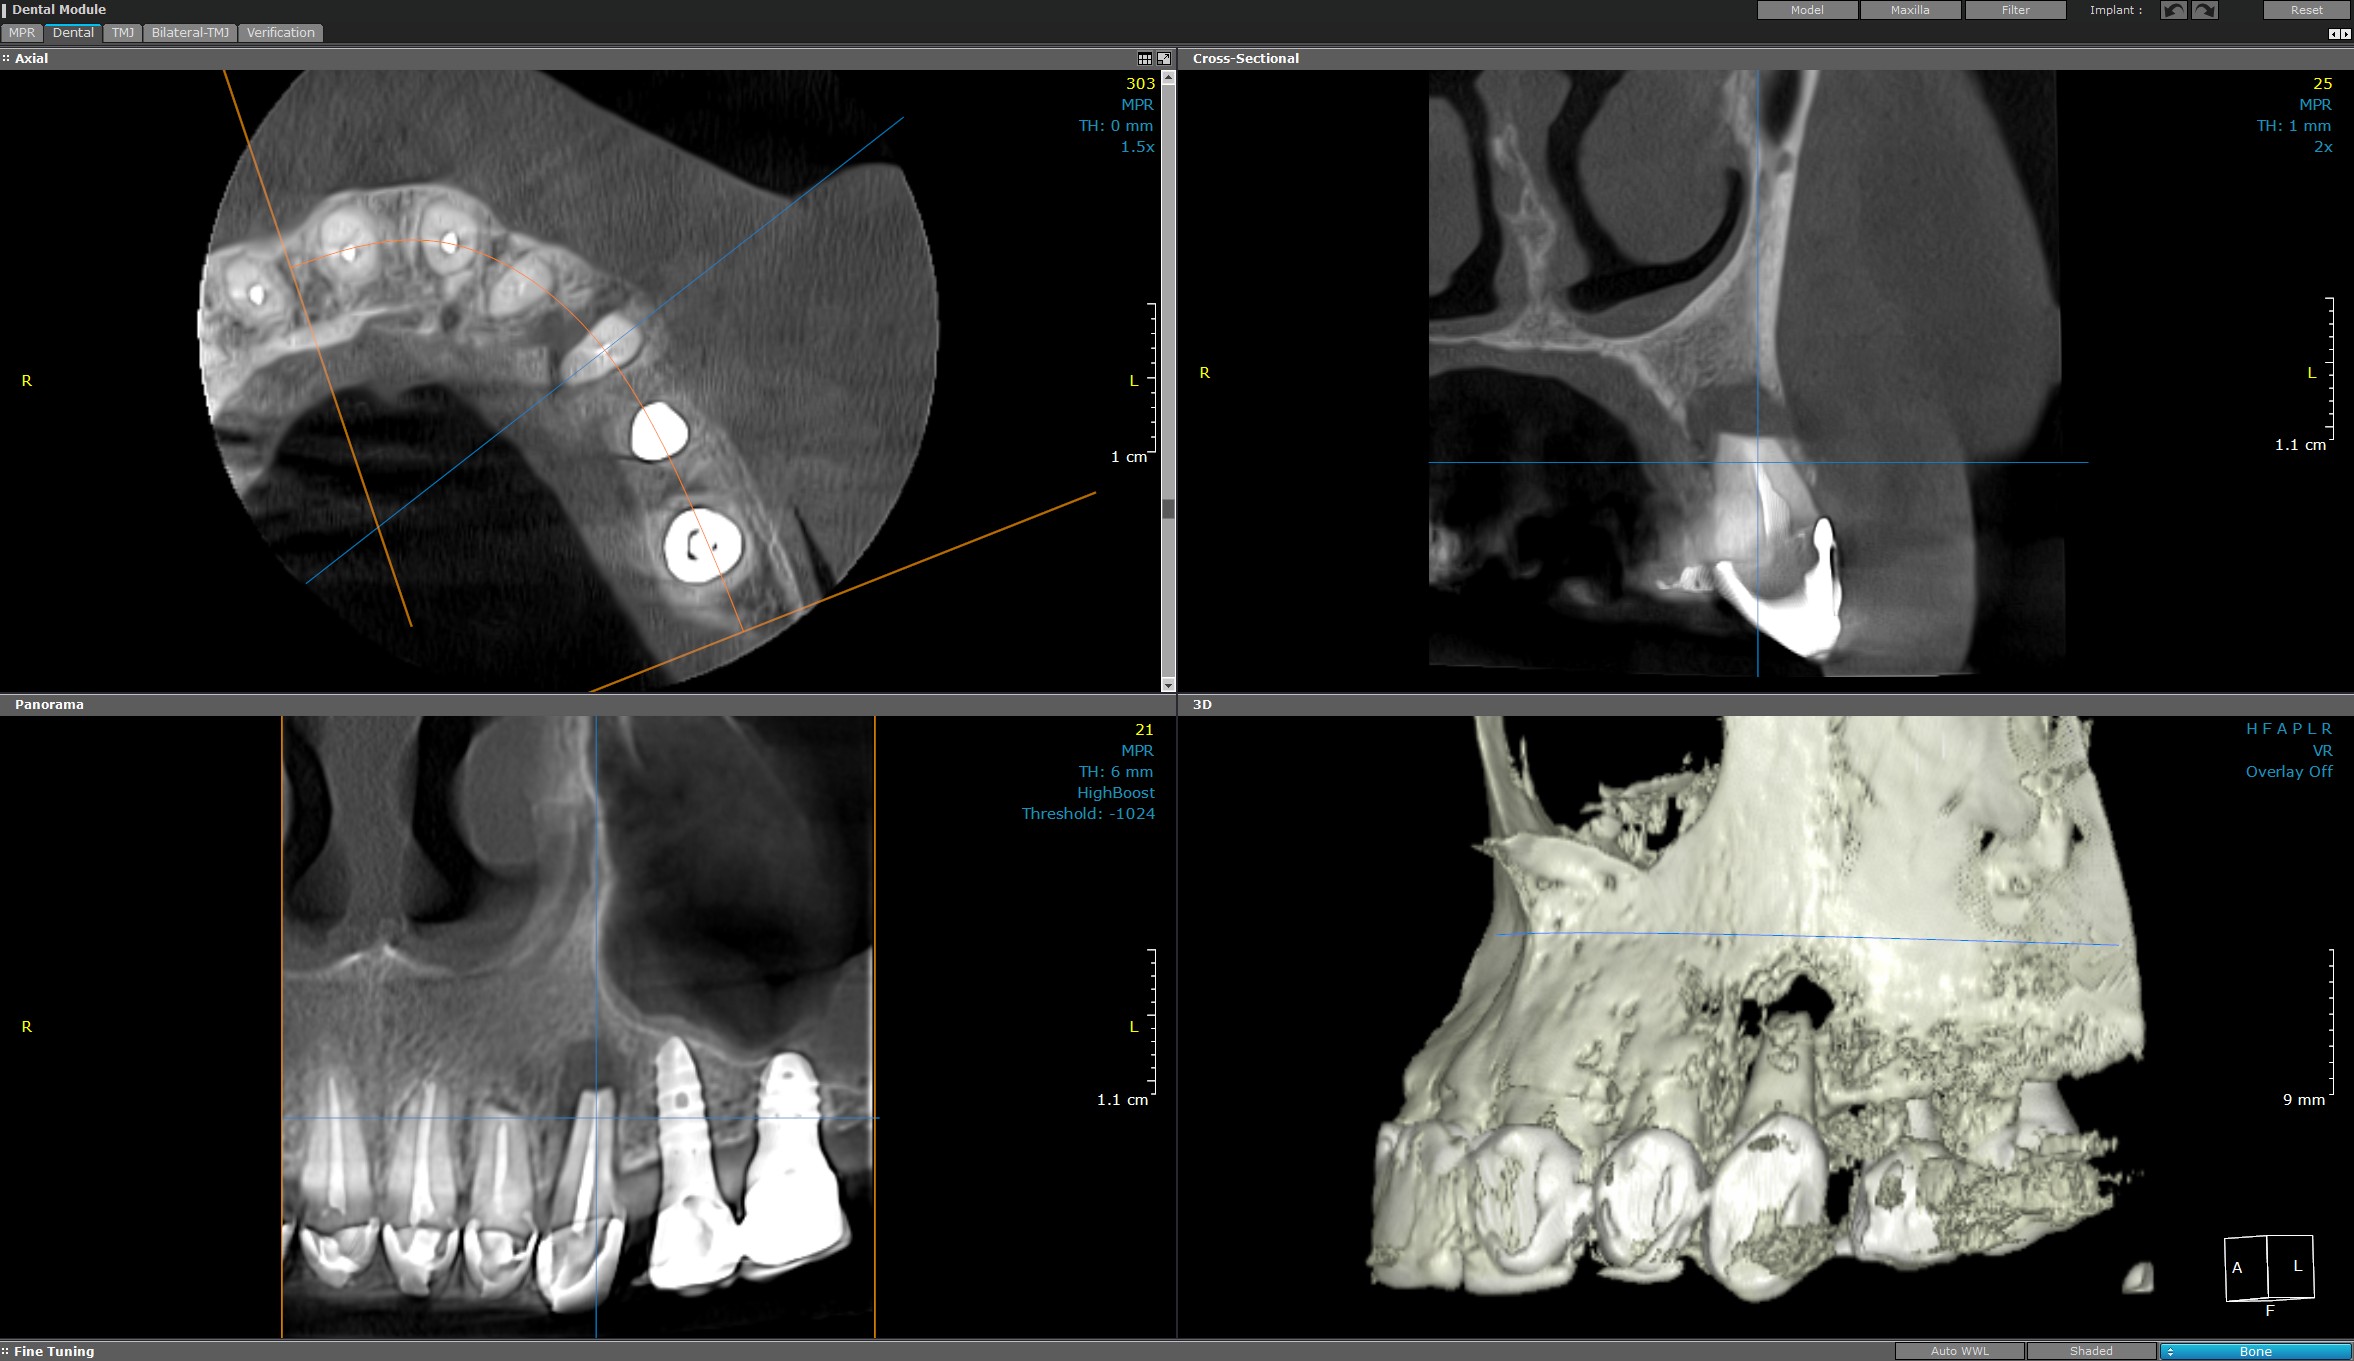

CT maxilar/mandibular sau bimaxilar (Computer Tomograf)

Furnizează imagini detaliate și precise cu privire la structurile dentare maxilare sau mandibulare, esențiale pentru diagnostic și planificarea tratamentelor dentare complexe.

Procedura este rapidă, non-invazivă și nedureroasă, folosind o tehnologie avansată de scanare.

Aceasta este utilizată la evaluarea preoperatorie a osului maxilar, planificarea implanturilor dentare și la stabilirea densității osoase, detectarea fracturilor, tumorilor, a infecțiilor și raportului acestora cu structurile anatomice învecinate acestora